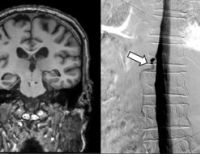

- 원인 못 찾던 뇌출혈 환자 4명, ‘뇌척수액 정맥 누공’으로 정밀진단, 세브란스서 모두 쾌차

- 연세대 세브란스병원이 ‘뇌척수액 정맥 누공’ 환자의 진단과 치료에 국내 최초로 성공했다. 이 질환은 자발성 두개내 저압증의 드문 형태 중 하나로 ...